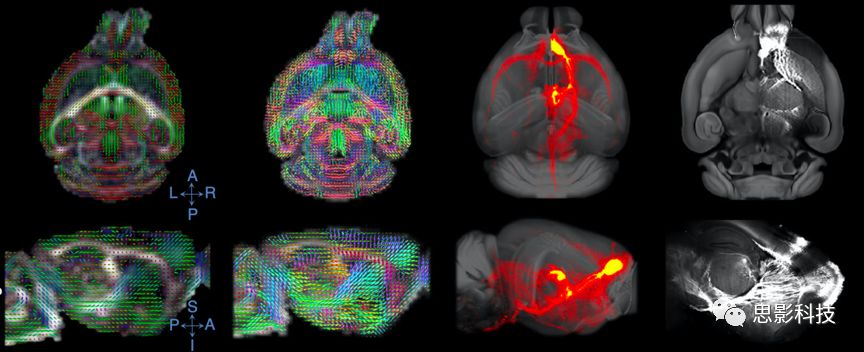

3、纖維追蹤

思影可根據(jù)不同的數(shù)據(jù)類型以及客戶的不同需求,可采取多種彌散模型(如彌散張量模型DTI、約束球形反卷積CSD、彌散譜成像DSI等等)

基于不同模型的確定性纖維追蹤

基于不同模型的概率性纖維追蹤